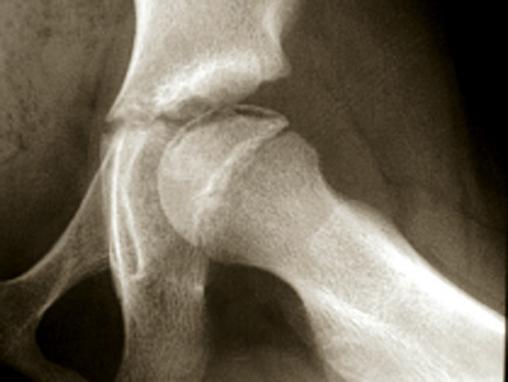

Ostéochondrite de hanche gauche au stade de début. Il s'agit d'une fracture sous-chondrale qui inaugure la douleur et donne un aspect radiographique en "coup d'ongle", c'est-à-dire un liseré noir juste sous l'os sous-chondral de l'épiphyse fémorale.